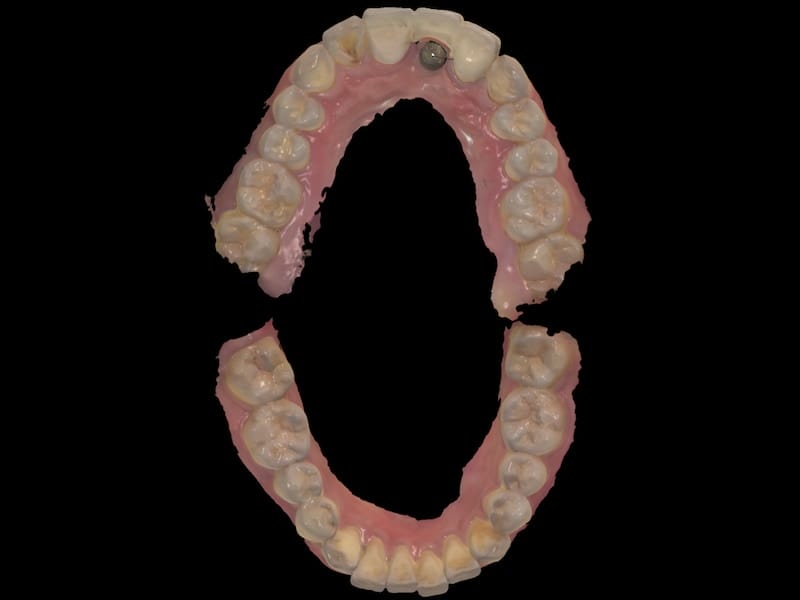

植入後等待大約四個月左右,植牙牙根和齒槽骨的骨整合完成,我們就可以開始製作假牙。牙科數位科技的進步,能夠讓我們利用電腦數位口內掃描的方式執行假牙製作流程。並且有很專業的牙技師配合,除了精準、效率,我們也能讓成品更加擬真。

利用數位口腔掃描,快速獲得口內上下顎 3D 模型 數位口掃 3D 模型,連咬合狀態也能清楚呈現